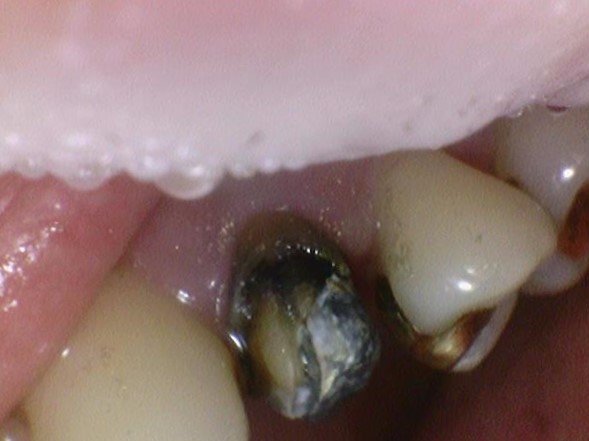

![[서울역/광화문] 오래된 크라운에 음식물이 많이 껴요 →해결방법은? 관련 이미지 3](https://pub-9f2bb3498faf4d1d8714b41df24753e3.r2.dev/content/clinics/archive/rseeanjxfu/naver_blog/yonseiyegam/assets/by_hash/4818d85b13d3a81c2ba215de990c61668331e6e2a690b8e6dba5148ebd0d391b.jpg)

오래된 금 크라운(왼쪽사진), 금크라운을 뜯은 상태(오른쪽 사진)